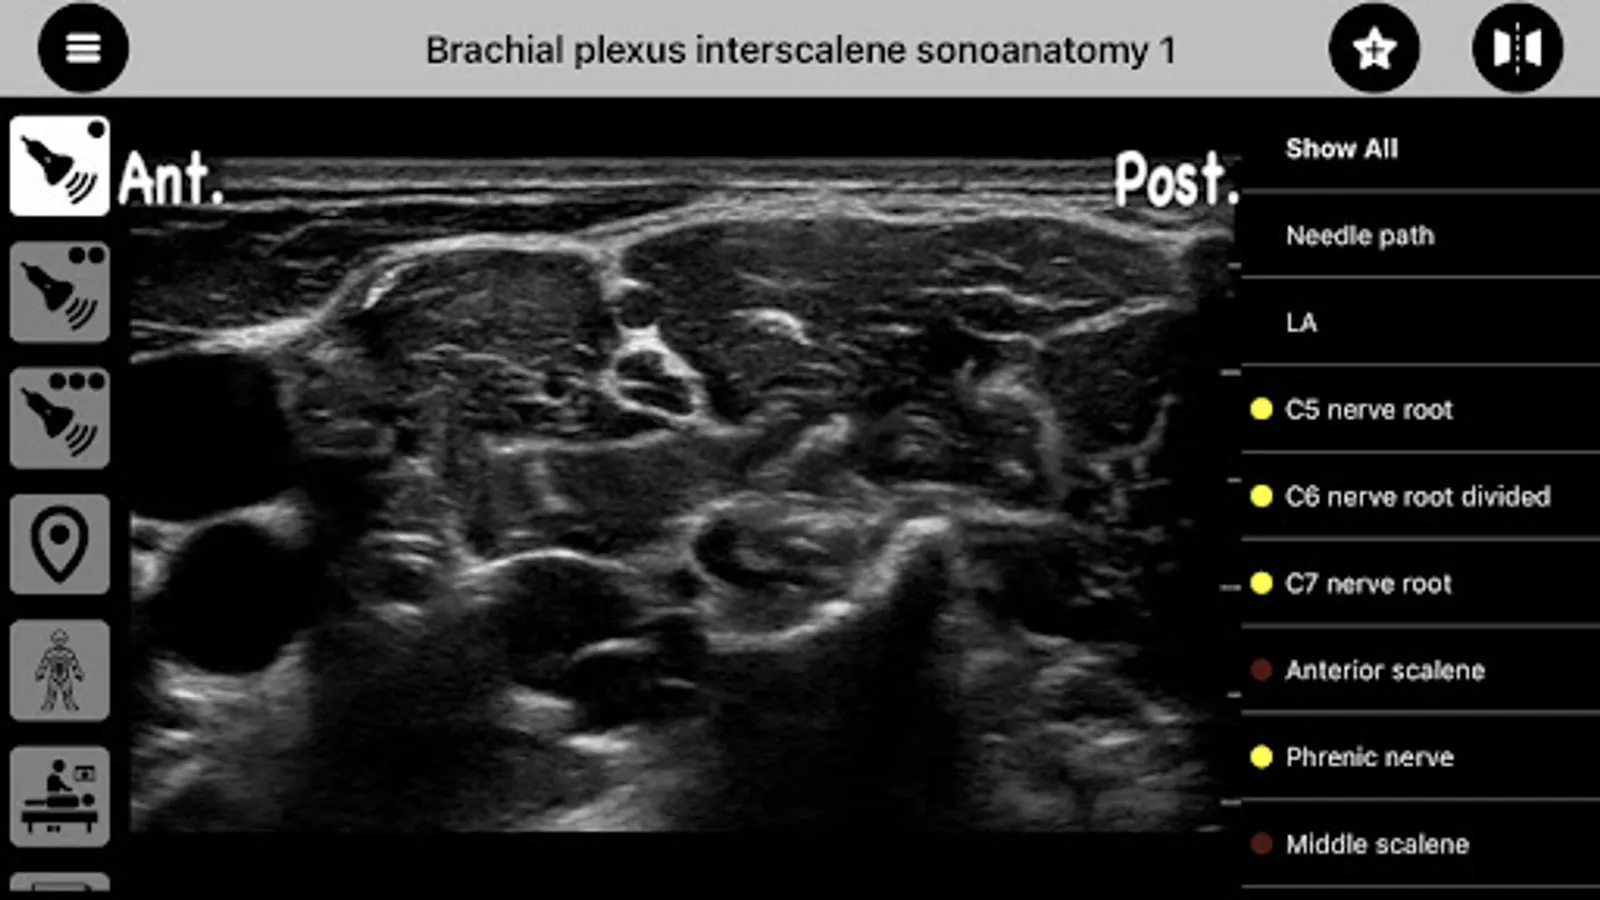

AnSo helps identify not only the target structures but all the surrounding sonoanatomy. This more comprehensive understanding of the sonoanatomy helps detect anatomical variability, improves the safety and efficacy of procedures, and facilitates learning and teaching.

- over 250 ultrasound images with over 1500 sonoanatomy colour overlays,